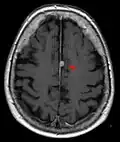

Brain regions on T1 MRI -

T1 (note CSF is dark) with contrast (arrow pointing to meningioma of the falx) -